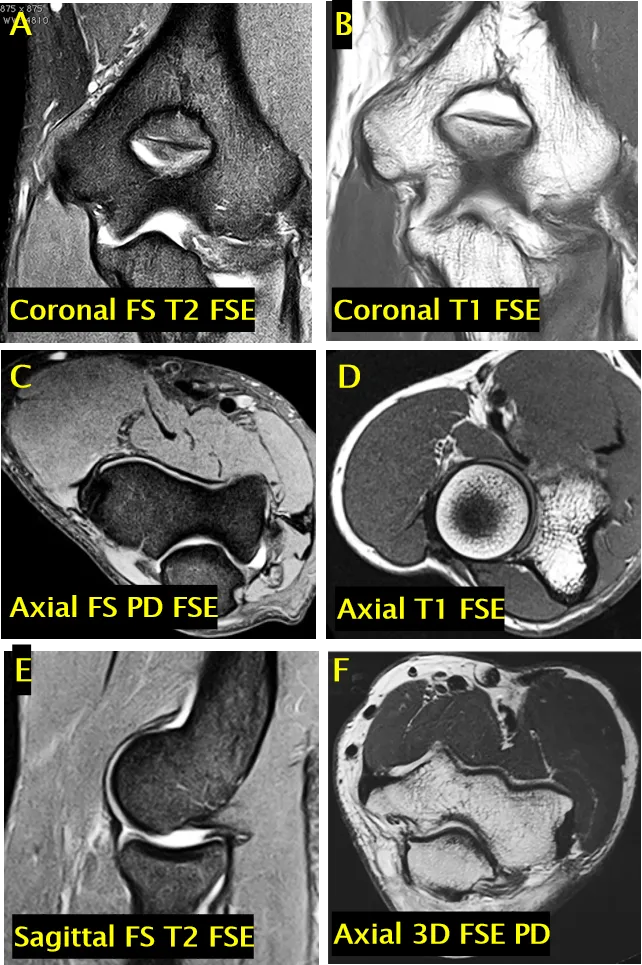

检查参数设置:

5. 冠状面:脂肪抑制 T2 加权快速自旋回波序列(FS T2 FSE)、T1 加权快速自旋回波序列(T1 FSE)

6. 轴面:脂肪抑制质子密度加权快速自旋回波序列(FS PD FSE)、T1 加权快速自旋回波序列(T1 FSE)、三维快速自旋回波质子密度加权序列(3D FSE PD)

7. 矢状面:脂肪抑制 T2 加权快速自旋回波序列(FS T2 FSE)